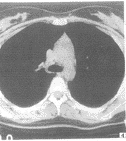

图3 男,5岁。胸腺似梯形,两外缘平直

形态:胸腺分左右两叶,多不对称,整个胸腺呈上窄下宽的三角形。96%患者胸腺CT扫描很少见到两叶之间的结缔组织分隔,胸腺形态随年龄变化及其周围纵隔和肺结构大小、形态改变而改变,由方形或梯形(图3)逐渐呈新月形、烧杯形、箭头形(图4),其前缘可宽可窄,本组病例前缘最宽达5cm,最小呈线样。两外缘形态88%为内凹或平直,12%一侧外缘或两侧外缘呈弧形外凸,后缘不同程度伸沿到纵隔大血管间隙内呈波浪状。两叶胸腺长轴夹角78%呈锐角,22%呈钝角。